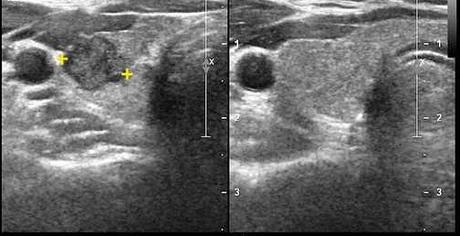

Tiroides normal.

Foto izquierda: corte transversal: el lóbulo piramidal en ubicación paramediana derecha (punta de flecha). Foto derecha: corte longitudinal: el lóbulo piramidal pre-laríngeo izquierdo se continúa imperceptiblemente con el istmo (c: craneal; i:istmo).